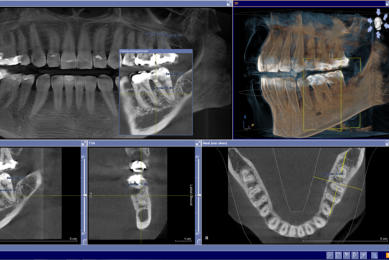

Für den Zahnarzt haben Röntgenaufnahmen einen unverzichtbaren Stellenwert in der Diagnostik und Behandlungsplanung. Für die Implantologie und viele andere zahnärztliche Bereiche bietet das digitale Röntgen eine optimale Möglichkeit der Vorplanung und Unterstützung während der Behandlung. Digitale 2D-Röntgenbilder und DVT´s/ 3D-Röntgenbilder können wir in besonders hoher digitaler Qualität und geringer Strahlendosis durchführen.

sehr hohe Auflösung und Kontrast sehr geringe Strahlenbelastung sofortige Bilddarstellung in Echtzeit optimale Vergrößerungsmöglichkeiten umfangreiche Bildnachbearbeitung punktgenaue Vermessung von Strecken gemeinsame Ergebnisauswertung mit dem Patienten Hochauflösende Panoramaaufnahme:

Anwendungsgebiete für die 3D-Diagnostik in unserer

Zahnarztpraxis Celle sind:

Implantologie Endodontie spezielle Parodontologie Chirurgie Zahnersatz Kieferorthopädie